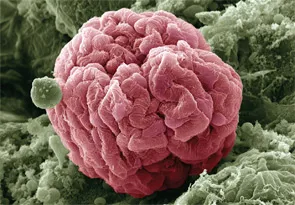

Você sabia que injeções cosméticas podem causar hipercalcemia e insuficiência renal anos após o procedimento? Descubra mais sobre os riscos e tratamentos dessa complicação em nosso novo post no blog!